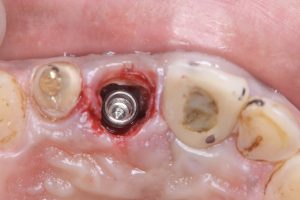

土曜日朝、前歯の抜歯即時

切歯管が近接しているから慎重にがテーマ!

その前に、部分抜歯し唇側束状骨の吸収を防ぐ!

色々な名称あり、ソケットシールドやらルートメンブレンやら他もあり